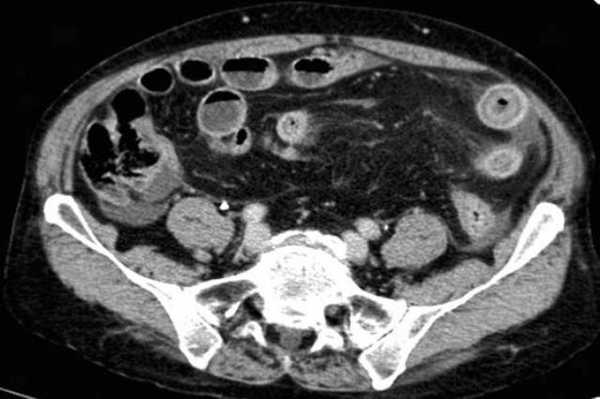

Мальротация кишечника (нонротация) у мужчины 39 лет.

(а, б) Тощая кишка — прямое продолжение двенадцатиперстной (стрелка, а), отсутствуют нормальные 3-й и 4-й сегменты двенадцатиперстной кишки, а также двенадцатиперстно-тощекишечный переход (звездочка, б).

(в, г) Петли тонкой кишки (прямые стрелки) лежат в левой половине брюшной полости, а ободочная кишка (изогнутые стрелки) — в правой половине. Заворот средней кишки у мальчика 11 лет.